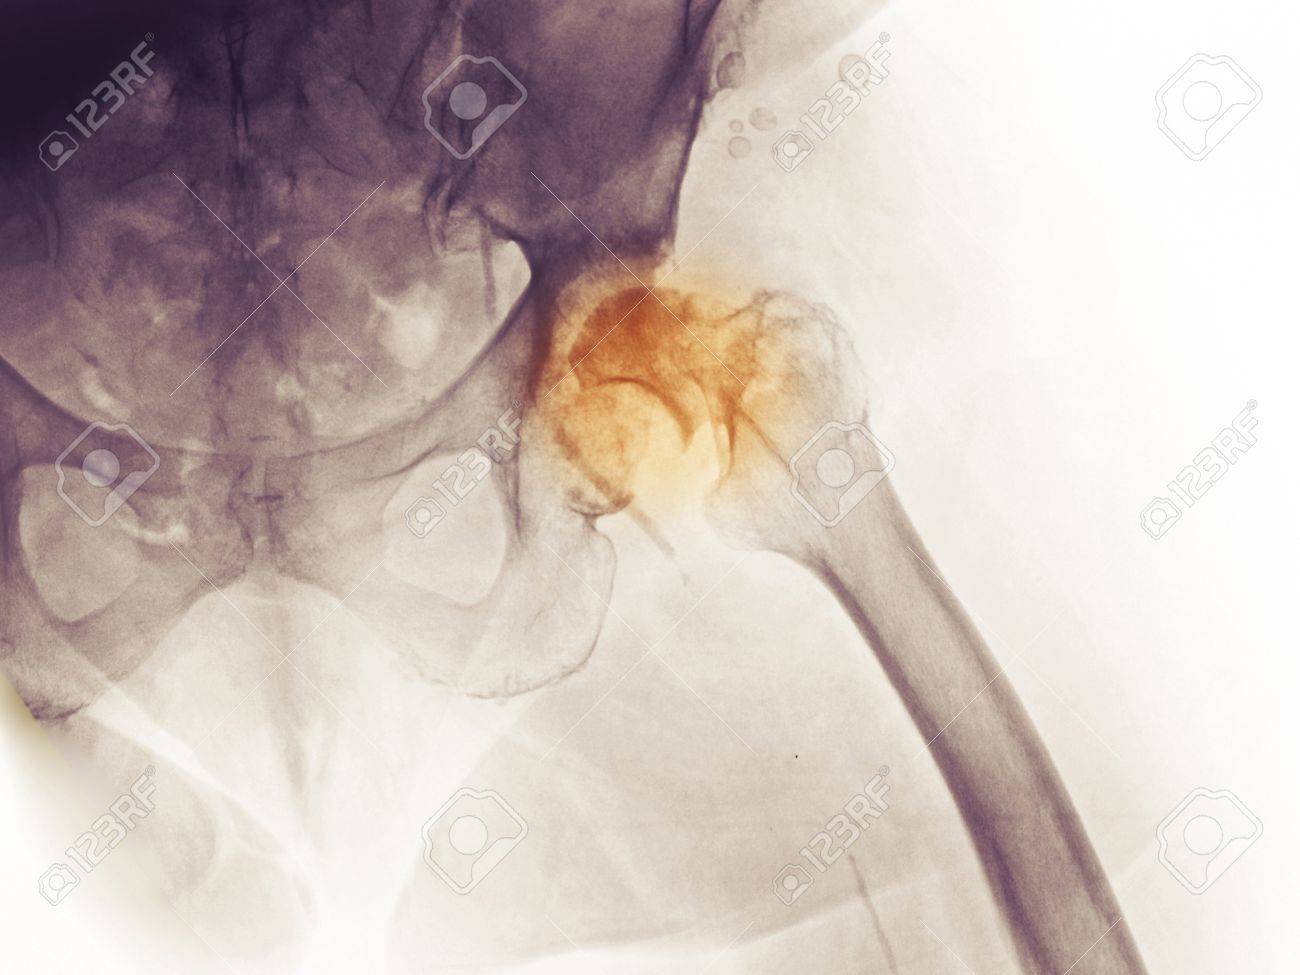

Geschichte der huefte. Bereits 1938 implantierte Philip Wiles eine Hüft-Totalprothese bei der er die Hüftgelenkpfanne mit einbezog. 1943 führte Austin Morre die Kopfprothese mit gefenstertem Schaft ein. Dabei wurde nur der Hüftkopf ersetzt.

Dadurch penetrierte die Prothese jedoch langsam durch das Becken. Die Gebrüder Judet ersetzten den Hüftkopf 1946 durch Plexiglas. Eine weitere Modeentwicklung schloss einige Jahre später im wahrsten Sinne des Wortes dann außer dem Oberkörperbereich die Hüfte mit ein.

Der Hüftgelenksersatz ist eine der erfolgreichsten Operationen in der Geschichte der Orthopädie. Bei korrekter Indikationsstellung und Durchführung sind Erfolgsraten von weit über 95 zu erwarten sowie bei einer weit überwiegenden Anzahl der operierten Patienten eine Haltbarkeit der Endoprothese von mehr als 15 Jahren. Im Leben des Menschen wechseln Yin und Yang Phasen immer wieder ab.